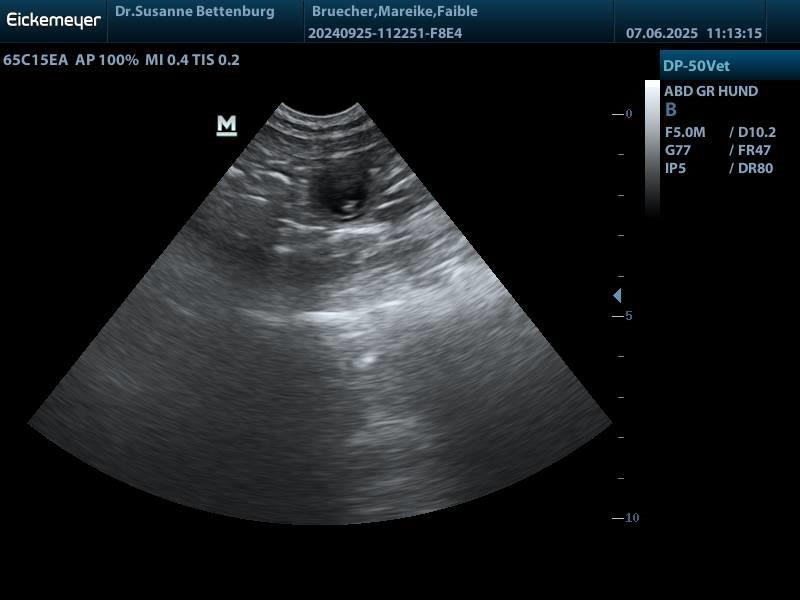

Juhuu Faible ist tragend. Wir freuen uns mitte Juli 2025 auf liverfarbende Welpen

Faible wurde am 18 Mai von Hugo gedeckt die Welpen werden um den 18. Juli geboren und dürfen ab der 2ten September Woche ausziehen

der I-Wurf ist für Sommer 2025 mit Faible geplant. Sie wird ca. Mai läufig. Es werden nur braune Welpen erwartet